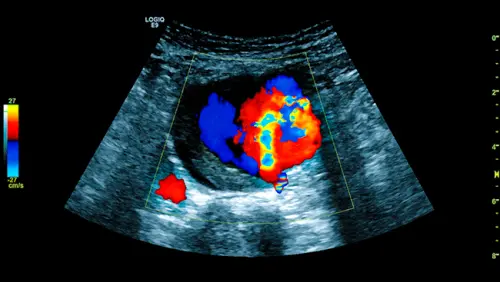

Дуплексне сканування дає одночасно дві картини. B-режим показує стінку судини, наявність кальцинованих бляшок, пристінкового тромбу або розшарування. Доплер вимірює швидкість і характер потоку — дозволяє виявити стеноз гирл ниркових і клубових артерій, оцінити колатеральний кровотік. Саме тому метод є першою лінією діагностики як аневризматичної хвороби, так і облітеруючого атеросклерозу.

Дослідження виконується на ультразвуковому апараті Mindray Resona 18 з матричними датчиками нового покоління. Апарат підтримує кольоровий та енергетичний доплер, а також імпульсно-хвильовий режим для точного вимірювання швидкості потоку в будь-якій ділянці судини.

Для аорти це важливо: стандартний конвексний датчик 3,5 МГц забезпечує достатню глибину сканування навіть у пацієнтів із надмірною вагою. Протокол дослідження відповідає рекомендаціям ESVS: вимірюється зовнішній діаметр аорти в двох площинах, оцінюється наявність тромботичних мас, стан стінки і кровотік у гирлах ниркових і загальних клубових артерій.